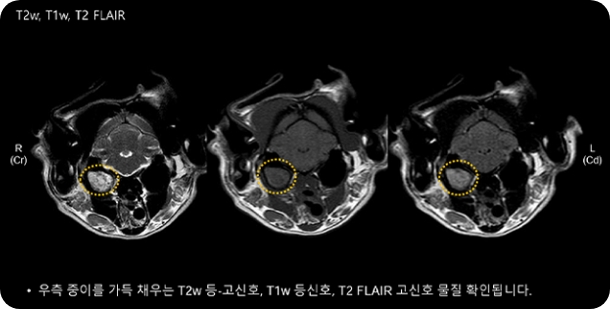

두부

뇌수막염, 뇌종양, 뇌수두증, 뇌출혈,

특발성 간질, 내이염 등

뇌수막염